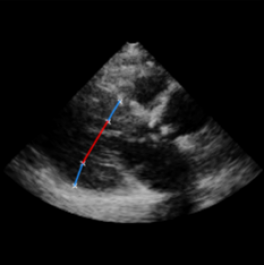

Left Ventricular Hypertrophy (LVH), one of the leading predictors of adverse cardiovascular outcomes, is the condition where heart’s mass abnormally increases secondary to anatomical changes in the Left Ventricle (LV) [10]. These anatomical changes include an increase in the septal and LV wall thickness, and the enlargement of the LV chamber. More specifically, Inter-Ventricular Septal (IVS), LV Posterior Wall (LVPW) and LV Internal Diameter (LVID) are assessed to investigate LVH and the risk of heart failure [21]. As shown in Figure 1 (a), four landmarks on a parasternal long axis (PLAX) echo frame can characterize IVS, LVPW and LVID, and allow cardiac function assessment. To automate this, machine learning-based (ML) landmark detection methods have gained traction.

It is difficult for such ML models to achieve high accuracy due to the sparsity of positive training signals (four or six) pertaining to the correct pixel locations. In an attempt to address this, previous works use 2D Gaussian distributions to smooth the ground truth landmarks of the LV [9, 13, 18]. However, as shown in Figure 1 (b), for LV landmark detection where landmarks are located at the wall boundaries (as illustrated by the dashed line), we argue that an isotropic Gaussian label smoothing approach confuses the model by being agnostic to the structural information of the echo frame and penalizing the model similarly whether the predictions are perpendicular or along the LV walls.